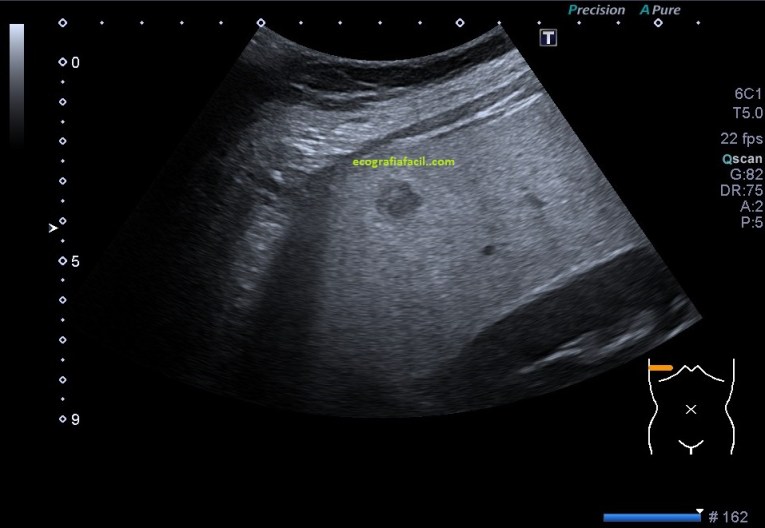

- Suelen ser lesiones solitarias, habitualmente isoecógenicas con el parénquima hepático. Formas atípicas de presentación presentan hipoecogenicidad o hiperecogenicidad.

En las imágenes puedes ver una LOE hepática que es cumple muchos criterios de los que hemos señalado arriba, pero el de la semiología, que es de los más importantes, no lo cumple. Se habla de que la HNF es una lesión isoecogénica con el parénquima hepático, ésta LOE es evidentemente hipoecogénica.

La LOE fue estudiada de manera protocolaria, haciendo medidas y aplicándose el Doppler, en este caso el modo angio o doppler power.

La paciente por tanto padece una esteatosis hepática, la lesión es hipoecogénica con respecto al parénquima hepático infiltrado de grasa, pero isoecogénica con el patrón ecográfico de la corteza renal, donde quiero ir a parar es a que la LOE de HNF sería isoecogénica con el parénquima hepático si eventualmente, éste, estuviese sano, es decir, si no estuviese infiltrado de grasa.